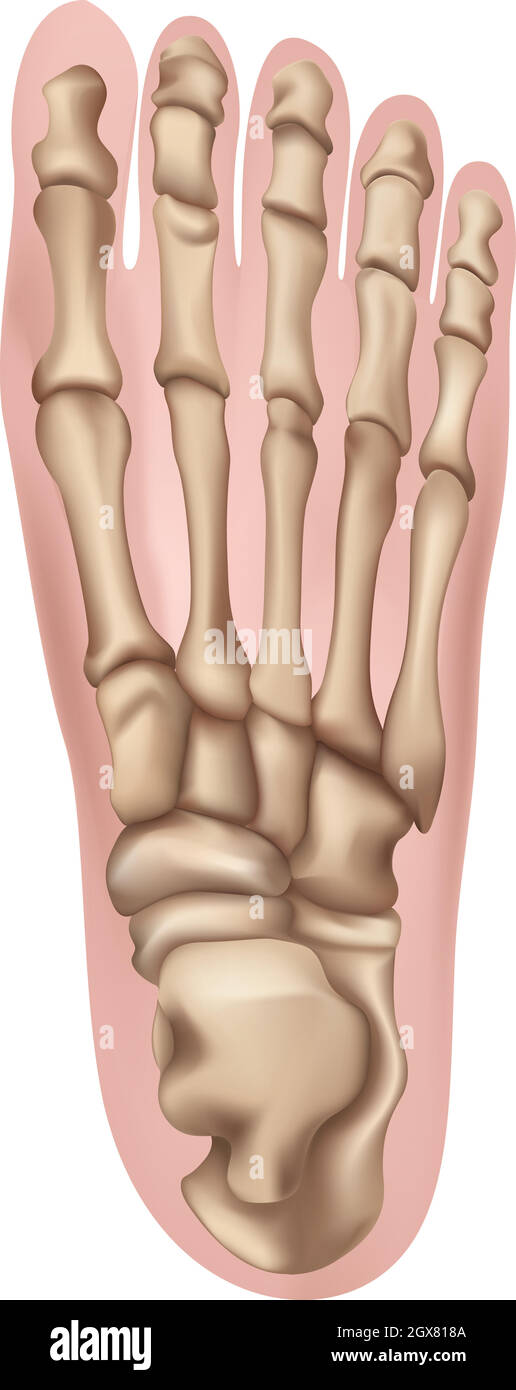

RF2WWY5XN–Os du pied humain avec le nom et la description de tous les sites. Vue supérieure. Anatomie humaine. Illustration vectorielle isolée sur un fond blanc.

RF2WNN754–Illustration médicale des principales parties des os du pied en vue antérieure, avec annotations.

RF2J65WT4–Anatomie du pied. Pied humain avec le nom et la description de tous les os et sites. Vue de dessus et vue latérale. Arcs des pieds. Anatomie du squelette. Vecteur

RF2R3WKY1–Illustration médicale des principales parties des os du pied en vue latérale, avec annotations.